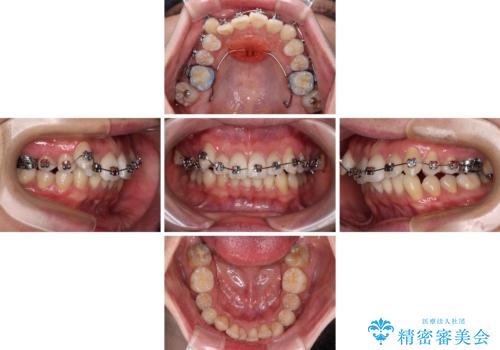

- 矯正装置

- メタルブラケット

また、左右ともに上顎最後臼歯が頬側に転移していたため、補助装置を用いて舌側に移動をさせながら、上顎前歯を引っ込むように移動させることとしました。

口元の突出感を解消させるため上顎左右第一小臼歯2本を抜歯して、ワイヤー装置にて矯正治療を行うこととしました。